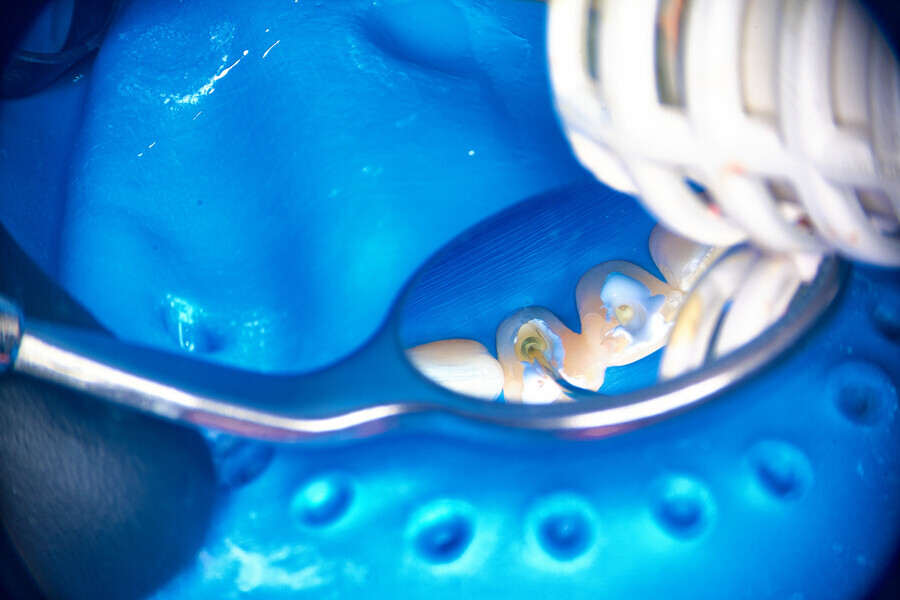

The patient was referred to Dr Witkowski’s dental office for removal of a broken file in the mesial canal and the final endodontic procedure (Fig. 9). Owing to difficulties and the risk of perforation, bypassing of the file was suggested to the patient and she agreed. Proper instrumentation was performed in both the mesial and distal aspects using the R25 RECIPROC blue (VDW; Fig. 10). After this step, extensive irrigation protocol was performed with sonic agitation and continuous irrigation (Fig. 11). The root canal system was then prepared for obturation and obturated using the piston technique (Fig. 12). This technique is capable of obturating even not mechanically instrumented spaces and is very easy to use, especially when there is an obstacle in the canal space such as a broken file (Fig. 13).